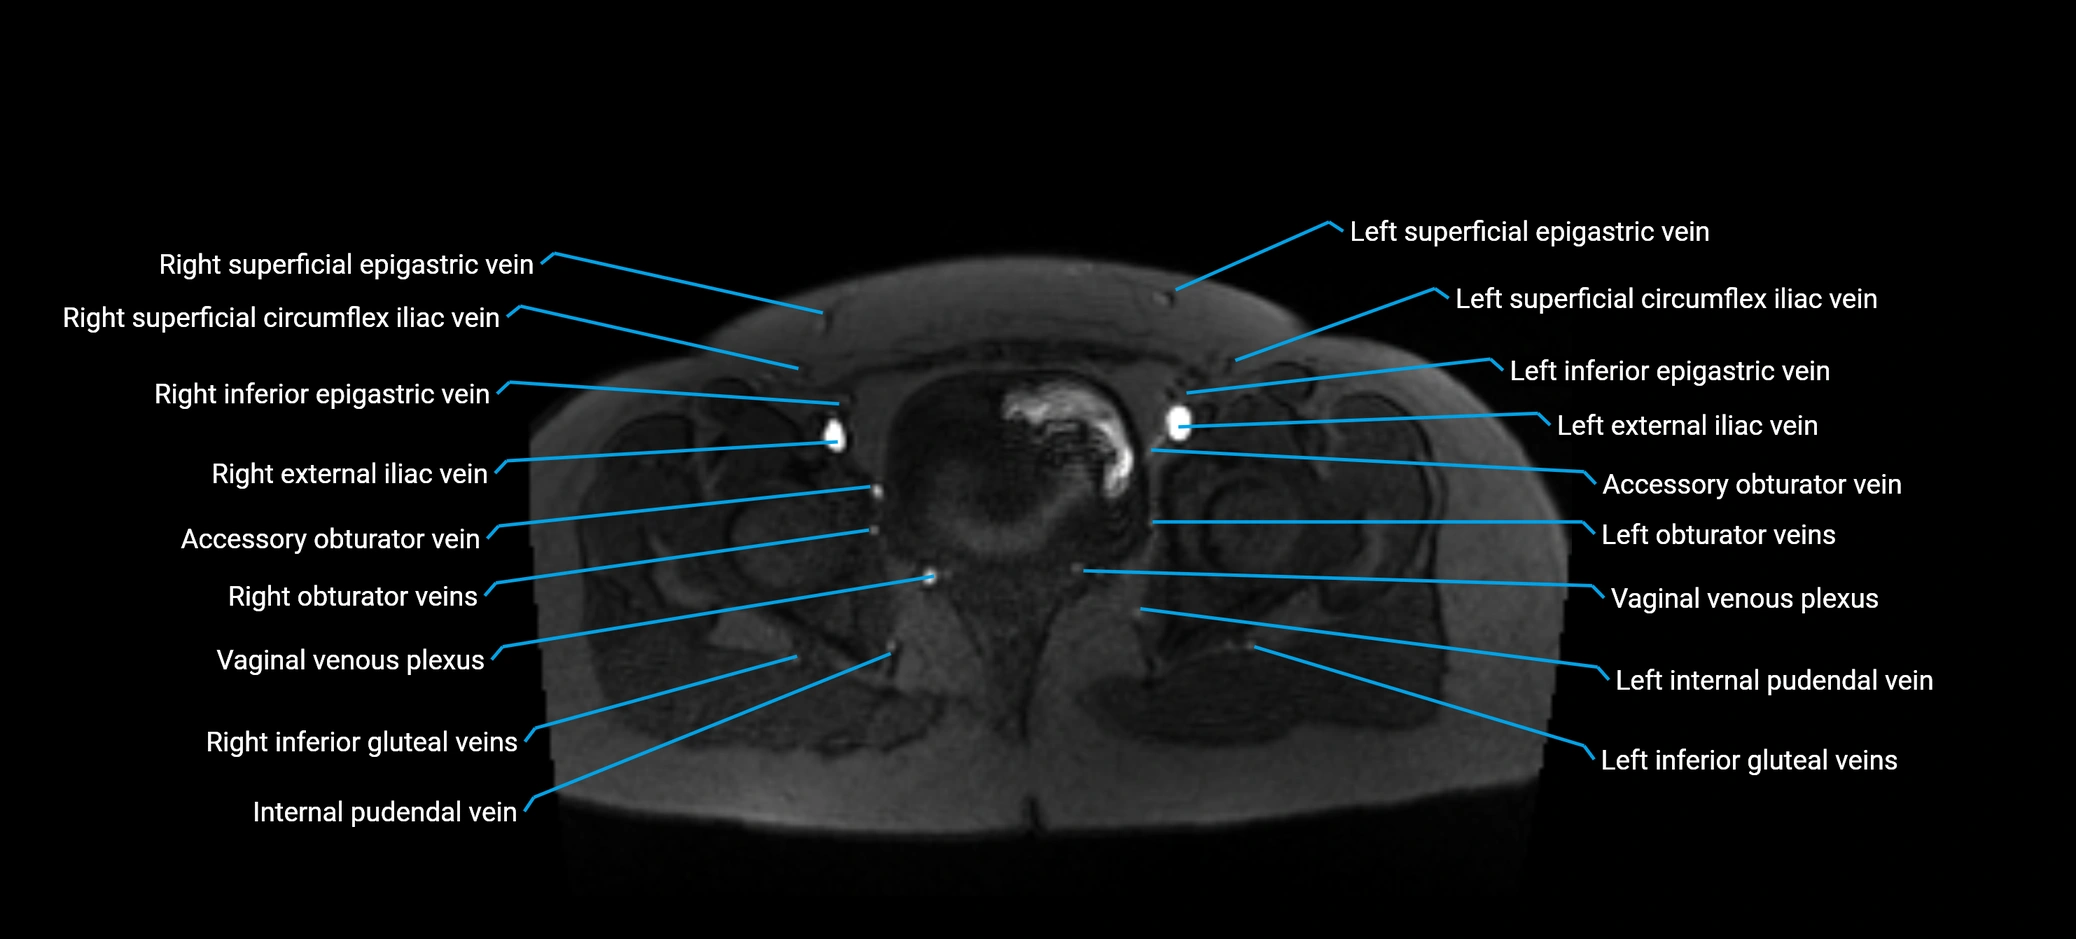

MRI image

image